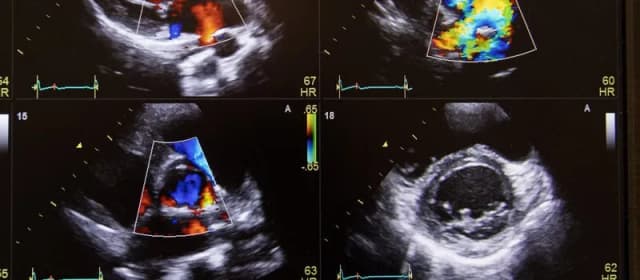

Tag badanie dopplerowskie na czym polega